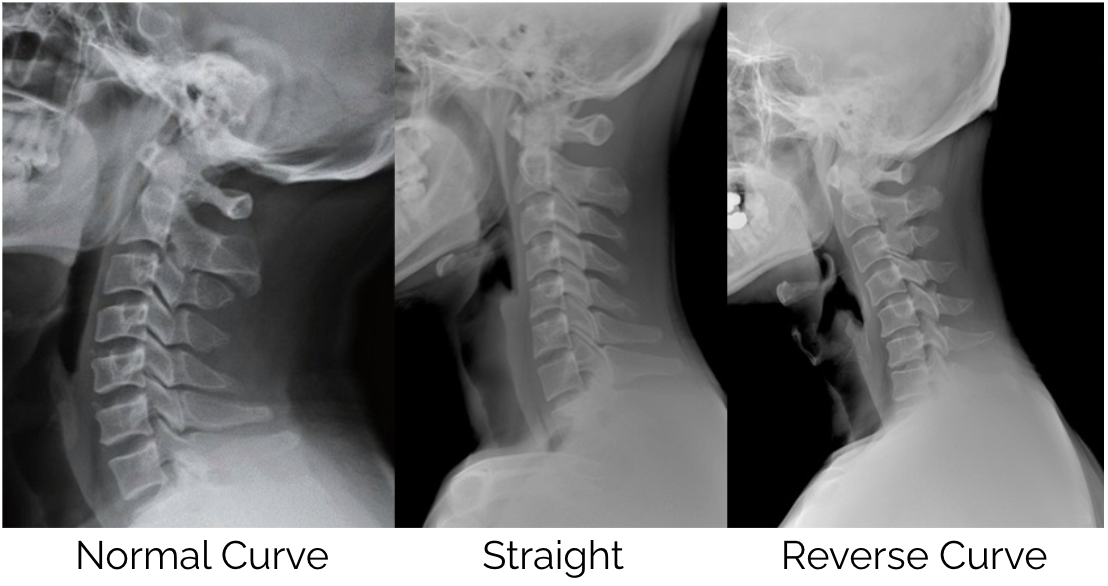

The consequences of sustained forward head posture extend well beyond local neck pain and muscle tension. Dr Hansraj’s research (1) also noted that spending several hours per day in poor posture can begin to alter the natural curvature of the cervical spine over time. A change that is far more difficult to address once it becomes established.

As Chiropractors, we have seen a shift over the past 10-20 years with more people losing the natural curve of the cervical spine and an increase in reversed curves which is a result of excessive time looking at handheld devices.